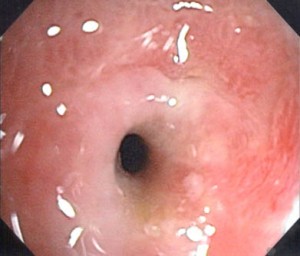

Endoscopy/ Gastroscopy

In this non-invasive technique, an endoscope is inserted through mouth into the upper gastrointestinal tract that includes esophagus, stomach and duodenum. This technique can help detect any tumor or ulcer in the stomach.

Picture 2 – Gastric outlet obstruction Image